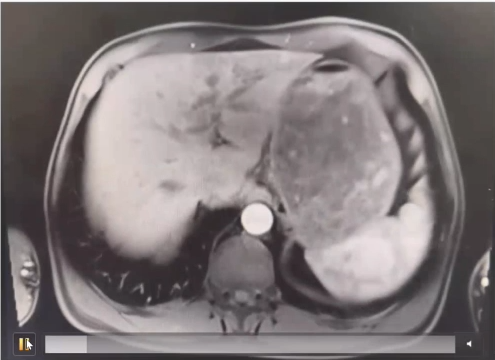

患者為57歲男性,近日就診于河北醫(yī)科大學第四醫(yī)院肝膽外科,入院后核磁檢查顯示十二指腸乳頭區(qū)軟組織信號腫物,考慮壺腹周圍癌可能,伴肝內外膽管擴張。壺腹部癌是生長在乏特壺腹、十二指腸乳頭、膽總管下端、胰管開口處、十二指腸內側壁癌的總稱,因腫瘤梗阻了膽總管和主胰管,通常會引起黃疸、膽囊腫大等。胰十二指腸切除術是治療胰頭及壺腹周圍腫瘤最為有效的外科術式,然而,該手術操作復雜,以“切除范圍大、吻合部位多、手術風險高”而著稱,被稱為腹部外科手術中的“珠穆朗瑪峰”。

▲病患入院影像檢查-動脈期